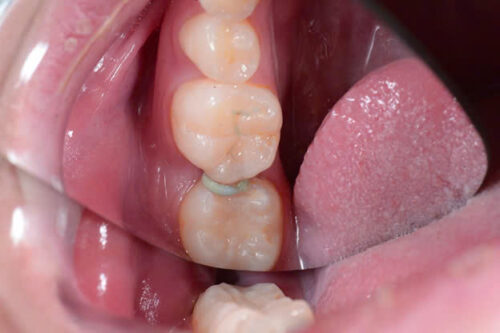

Bước 2: Tháo chun, làm sạch và tạo xoang trám bằng kỹ thuật đường hầm

Bước 3: Trám phục hồi